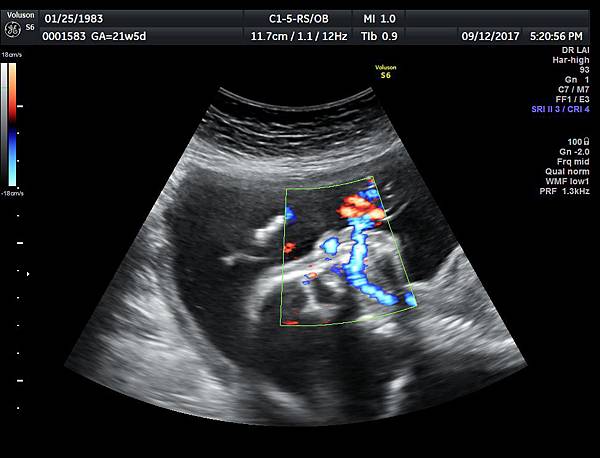

21w 6d right side cleft lip and palate and cleft uvula and brain anomaly < ACC and lissencephaly> images 3421

一個檢查如果要花很長的時間才能完成,這樣的檢查無法變成常規的篩檢方式,我已經在我的診所執行懸雍垂檢查一段時間,我檢查懸雍垂大約30 秒,前提是胎兒的臉最佳位置是側躺,其次是側躺偏向上,我的檢查步驟是上顎(含日後大門牙長出的位置)、舌頭、懸雍垂(= equal sign)(附圖1~8),如果超過60秒無法完成,只有兩個原因,一個是胎兒姿勢不適合或喉嚨羊水空間太小,這時候不要硬碰硬,只要先檢查其他部位,等待時機再回來即可,我的經驗是90%的cases都能順利完成這項檢查(肚皮厚的case真的是很難)。